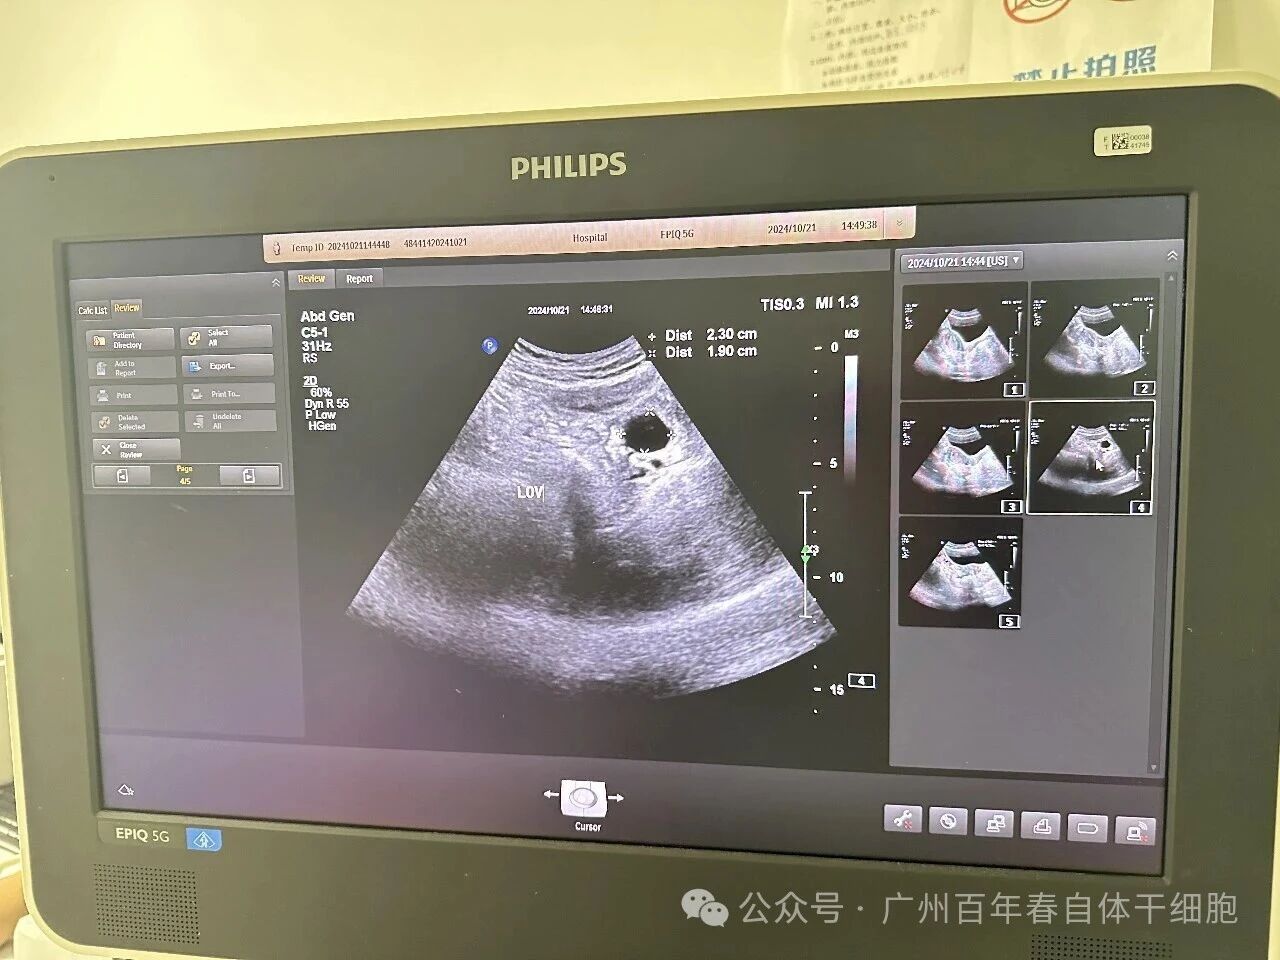

保健后两次监测B超结果都可见成熟卵泡及优势卵泡,卵巢体积增大,窦卵泡计数增多,雌二醇及AMH值逐渐上升。多次保健后更令人振奋的是,杨女士在停药后仍保持规律月经周期,且自然受孕成功,最终诞下健康婴儿。

△保健前后B超对比